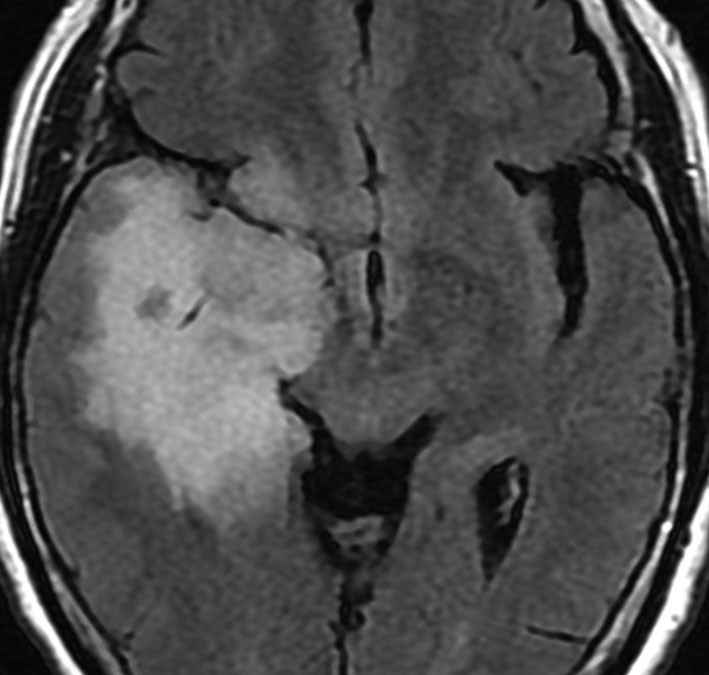

これは30歳くらいの若い女性にできた乏突起膠腫です。軽いけいれん発作を生じましたがその後は無症状です。上がT2強調画像で,下がガドリニウム増強像です。CTでは石灰化が散在していました。大脳深部をほとんど埋めるように腫瘍は浸潤して広がっています。脳外科の先生にこの患者さんが無症状だといっても信じてもらえないのですが本当です。

ほんの少しだけ腫瘍をとって(生検術)病理診断を確定しました。

腫瘍が大きすぎるので,認知機能を保つために,全脳照射30グレイとテモゾロマイド化学療法を2年しました。以来9年以上たちますが,とても頭の良い方でちゃんと働いておられます。

この患者さんから学ぶことはたくさんあります。この広範に伸展した腫瘍はおそらく10歳前後から存在したのだと想像されます。腫瘍が発見されず未治療だったからこそ,これまで通常の生活ができたのかもしれません。

また,グレード2の乏突起膠腫には限りなくグレード1に近い高分化型の腫瘍が存在するということです。乏突起膠腫は手術で完全摘出できれば治るのでしょうが,手術によって認知機能障害や高次脳機能障害を生じれば社会生活を一人ですることは難しくなります。分化型の乏突起膠腫は,正常の神経細胞や脳機能を破壊しないで浸潤増大しますから,脳の中にこんなに広がっても,何の症状も出さないということがあります。同じグリオーマでも膠芽腫などと比べれば大きな差があるのです。治療後の生存の質を考える時に,このような例があるということを思い出すことは大切です。